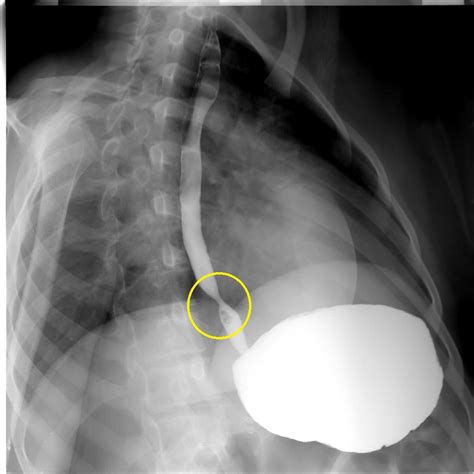

Diagnosis and Staging of Esophageal Cancer

Diagnosing esophageal cancer involves several steps, including:

• Endoscopy: A procedure where a flexible tube with a camera is inserted down the throat to examine the esophagus.

• Biopsy: A small tissue sample is taken during the endoscopy and examined under a microscope to confirm the presence of cancer.

• Imaging Tests: CT scans, PET scans, and MRI scans are used to determine the extent of the cancer and whether it has spread to other parts of the body.